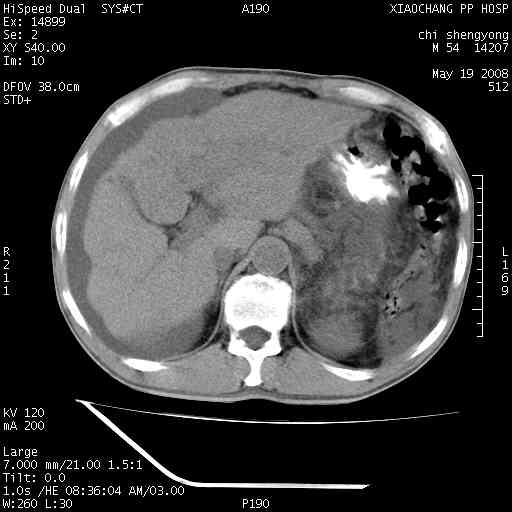

以下是引用zjzjr在2008-5-21 10:52:00的发言:[br]肝左叶巨块型肝癌伴门静脉左支瘤栓形成.肝硬化、腹水,胃底静脉曲张,脾术后改变。

以下是引用随光逐影在2008-5-21 16:20:00的发言:[br]1)肝左叶肝癌伴门静脉左支瘤栓形成,腹膜后淋巴结转移。2)肝硬化、腹水、胃底静脉曲张。3)胆囊炎。4)脾脏缺如,为切除术后所致。